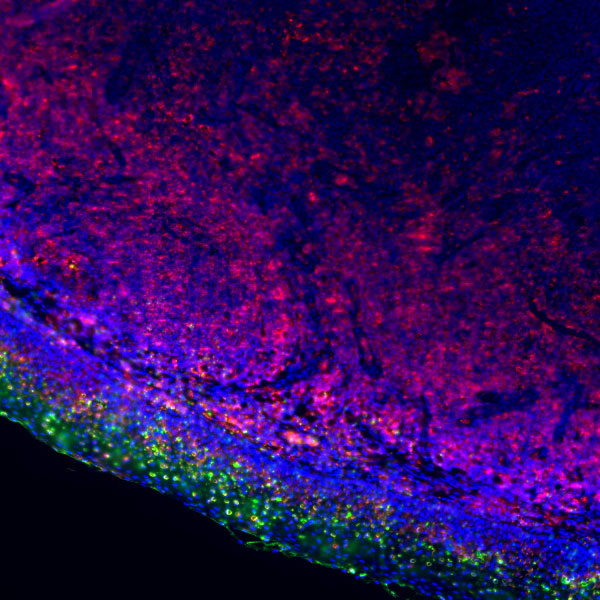

1 Antibody Specificity: The specificity of an antibody is reflected in three aspects: tissue specificity, cellular specificity, and subcellular localization specificity.

Typical example: Staining of paraffin-embedded human prostate cancer tissue sections with different PSAP antibodies:

Left panel: Strong cytoplasmic positivity in cancer cells, indicating correct cellular specificity and subcellular localization of the antibody.

Right panel: Weak membranous positivity in cancer cells, where the antibody shows correct cellular specificity but incorrect subcellular localization, suggesting inaccurate specificity.

Recommendation for Resolution: Prioritize antibodies with accurate tissue specificity, cellular specificity, and subcellular localization specificity, as this is the core principle for primary antibody selection.